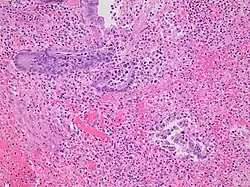

Pathology diagnosis of appendicitis can be made by detecting a neutrophilic infiltrate of the muscularis propria.

-

Micrograph of appendicitis and periappendicitis. H&E stain. -

Micrograph of appendicitis showing neutrophils in the muscularis propria. H&E stain. -

Acute suppurative appendicitis with perforation (at right). H&E stain.